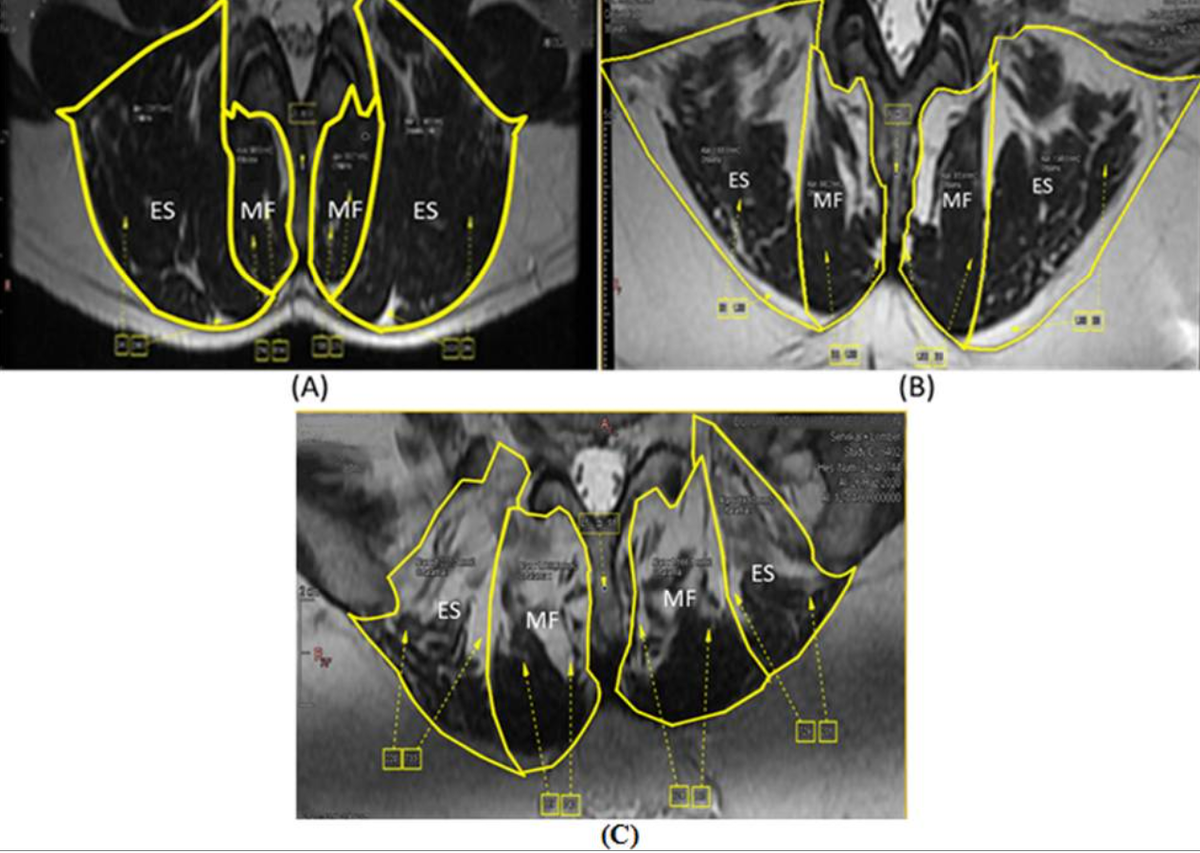

Степени жировой инфильтрации мышц по МРТ(желтым обведены мышцы, белые участки внутри - жировая дегенерация) A степень 1: жировая инфильтрация мышцы <10 %

B степень 2: жировая инфильтрация мышцы 10–50 %

C степень 3: жировая инфильтрация мышцы >50 %

MF - многораздельная мышца, ES - мышца, выпрямляющая позвоночник